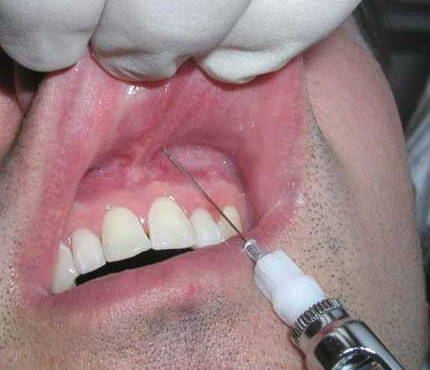

2 – kỹ thuật gây tê dây chằng để điều trị tủy răng.

Dùng kim 30, 27 hoặc 25 áp sát chân răng đâm vào rãnh lợi phía gần, đối với răng nhiều chân có thể đâm vào vùng chẽ chân răng, mặt vát kim hướng về phía chân răng và hợp với trục răng 1 góc 30 độ, sao cho đầu kim lách được vào giữa khoảng dây chằng, ấn kim đến lúc không thể xuống sâu hơn được nữa thì bơm chậm khoảng 0,2 ml thuốc tê, khi bơm sẽ có cảm giác rất nặng tay và cảm giác dội ngược trở lại, nếu không có cảm giác này thì điểm đâm kim chưa đúng và cần đâm lại. Sau đó làm tương tự với phía xa

Cần lưu ý rằng tiêm vào vùng này là rất cứng chắc, do đó có thể dùng ngón tay để ấn kim vào hoặc dùng kẹp để ấn kim vào

Gây tê dây chằng cho hiệu quả gây tê nhanh nhưng thời gian tê ngắn nên thường chỉ áp dụng để gây tê bổ sung cho các phương pháp khác